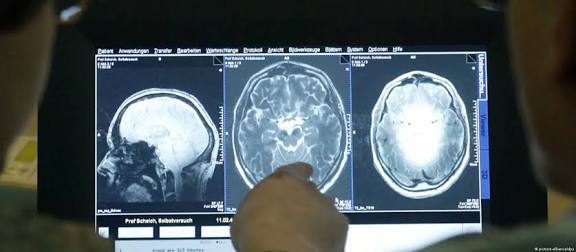

كيف يتم تشخيص مرض الزهايمر ؟

يُشخّص مقدمو الرعاية الصحية مرض الزهايمر المبكر بنفس طريقة تشخيص الزهايمر التقليدي حيث يجرون فحصاً جسدياً وعصبياً شاملاً كما أنه سيطرح عليك بعض الاسئلة لفهم صحتك و روتينك اليومي و يستخدم بعض الاختبارات مثل :

• اختبارات معرفية .

• تصوير مقطعي محوسب .

• تصوير الدماغ بالرنين المغناطيسي .

• وقد يستخدم فحص السائل النخاعي او تحاليل الدم للكشف عن مستوى الأميلويد والتاو.

وغيرها من الاختبارات حيث لا يوجد اختبار واحد يشخص مرض الزهايمر المبكر لكن تساعد تلك الاختبارات على استبعاد الحالات الأخرى التي تسبب أعراض متشابهة .